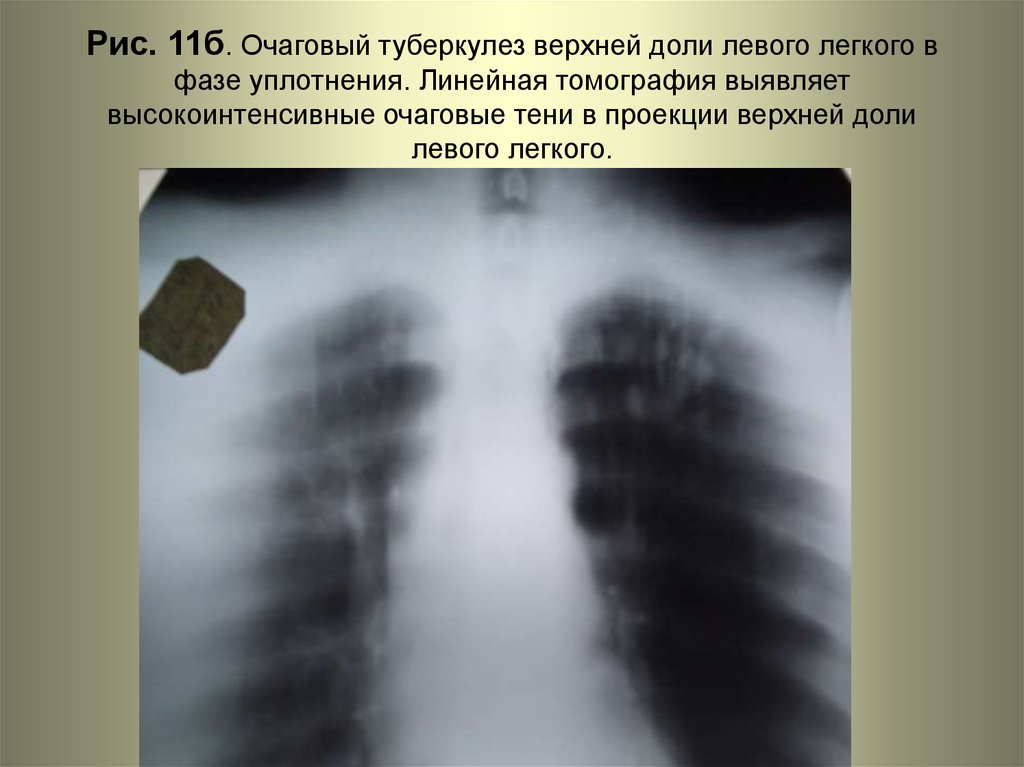

Иллюстрации по теме очагового и инфильтративного туберкулеза